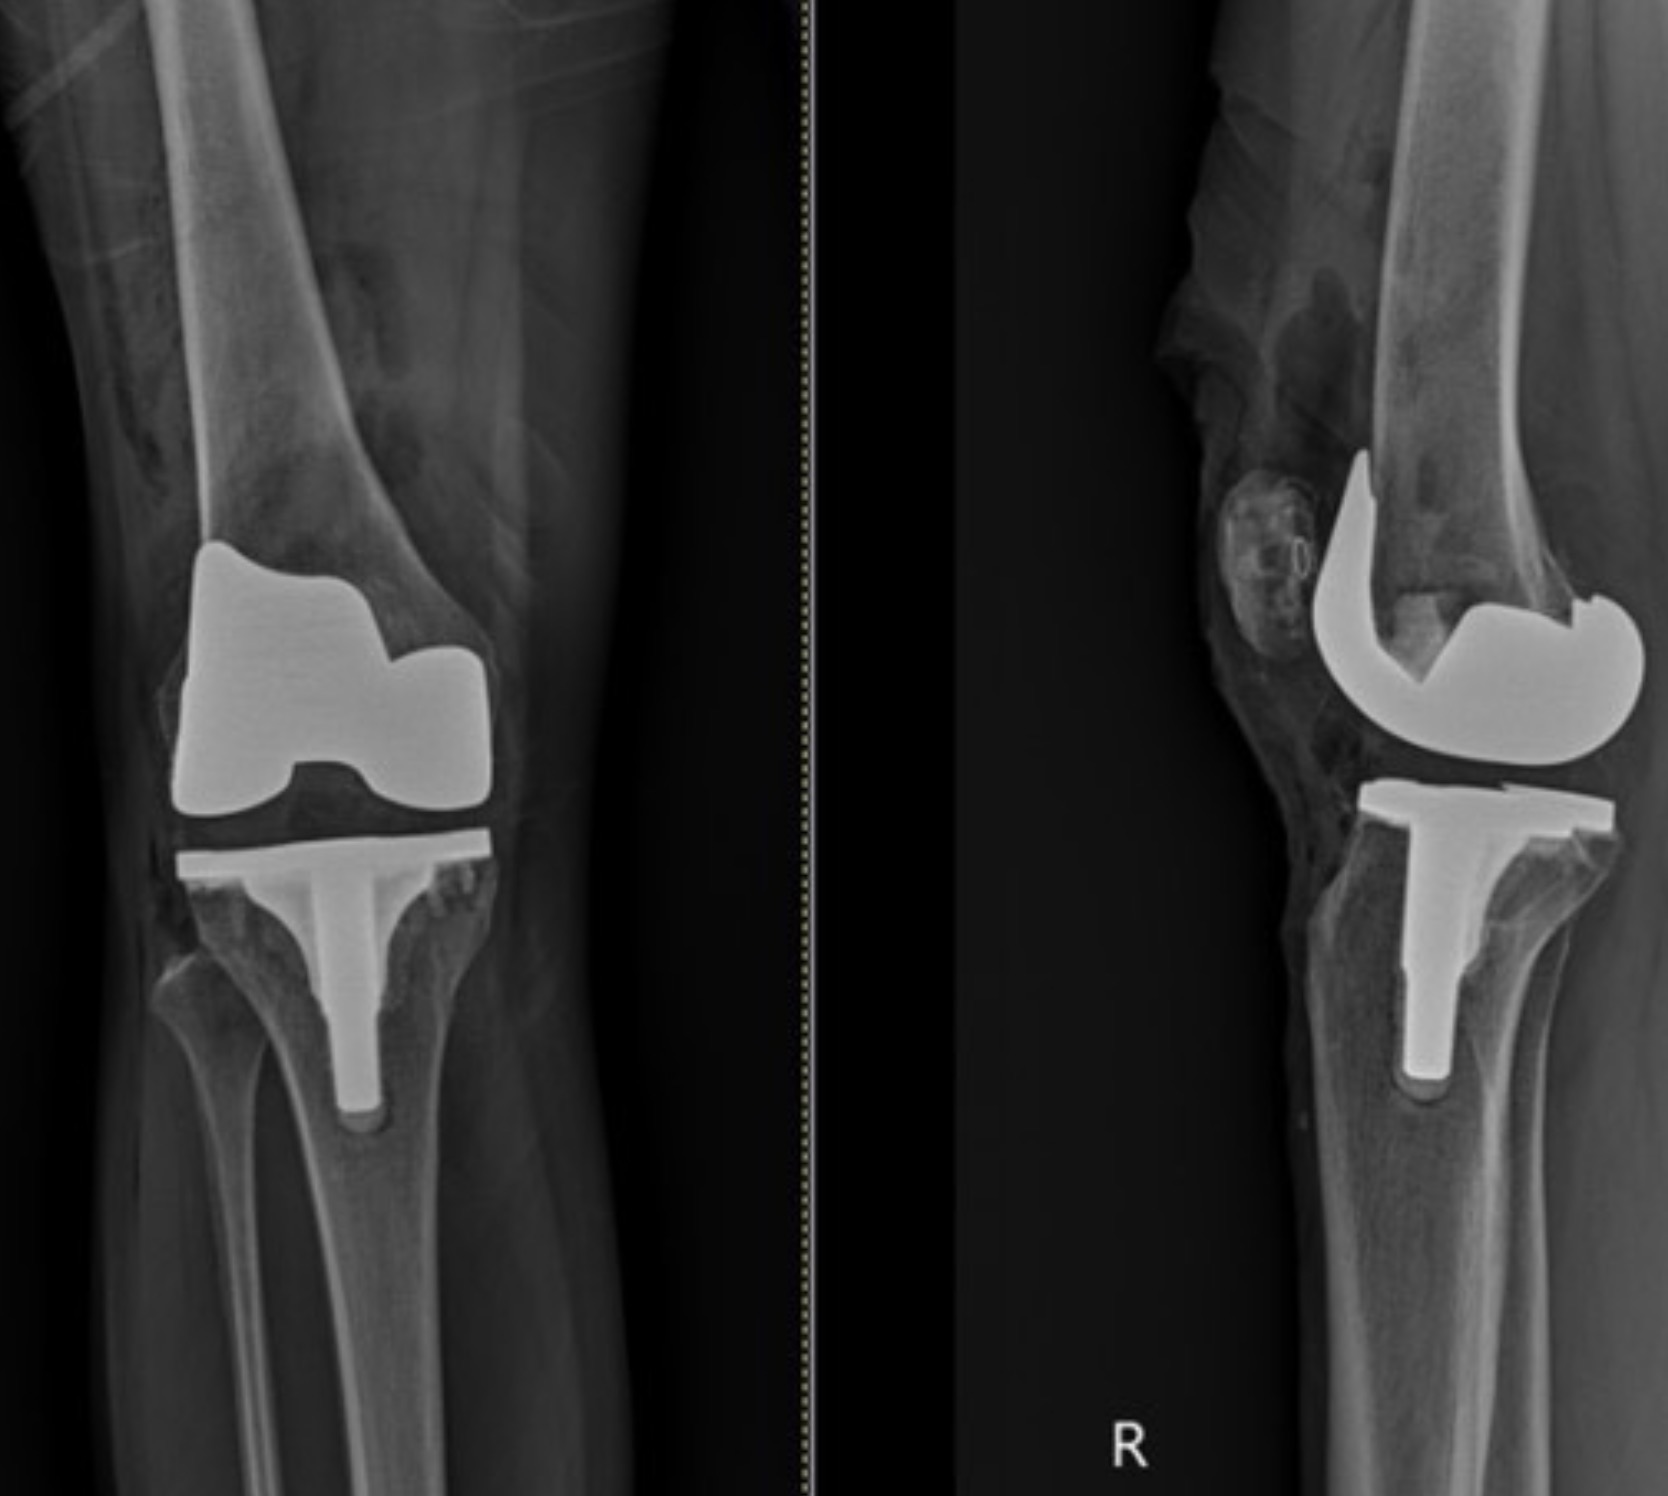

เป็นการผ่าตัดนำผิวข้อเข่าที่เสื่อมแตกออก แล้วใส่ผิวข้อใหม่ที่เป็นโลหะ–พลาสติกทางการแพทย์ที่แข็งแรงและปลอดภัย โดยไม่ต้องตัดกระดูกทั้งชิ้น แต่เปลี่ยนเฉพาะผิวข้อที่สึก

ข้อเข่าเทียมประกอบด้วย 3 ส่วนหลัก:

- ผิวข้อด้านบน (กระดูกต้นขา)

- ผิวข้อด้านล่าง (กระดูกหน้าแข้ง)

- แผ่นรองพลาสติกที่ช่วยให้ข้อเคลื่อนไหวลื่น

4) ใส่ข้อเทียม

ใช้โลหะ–พลาสติกทางการแพทย์ที่เข้ากับร่างกายได้ดี